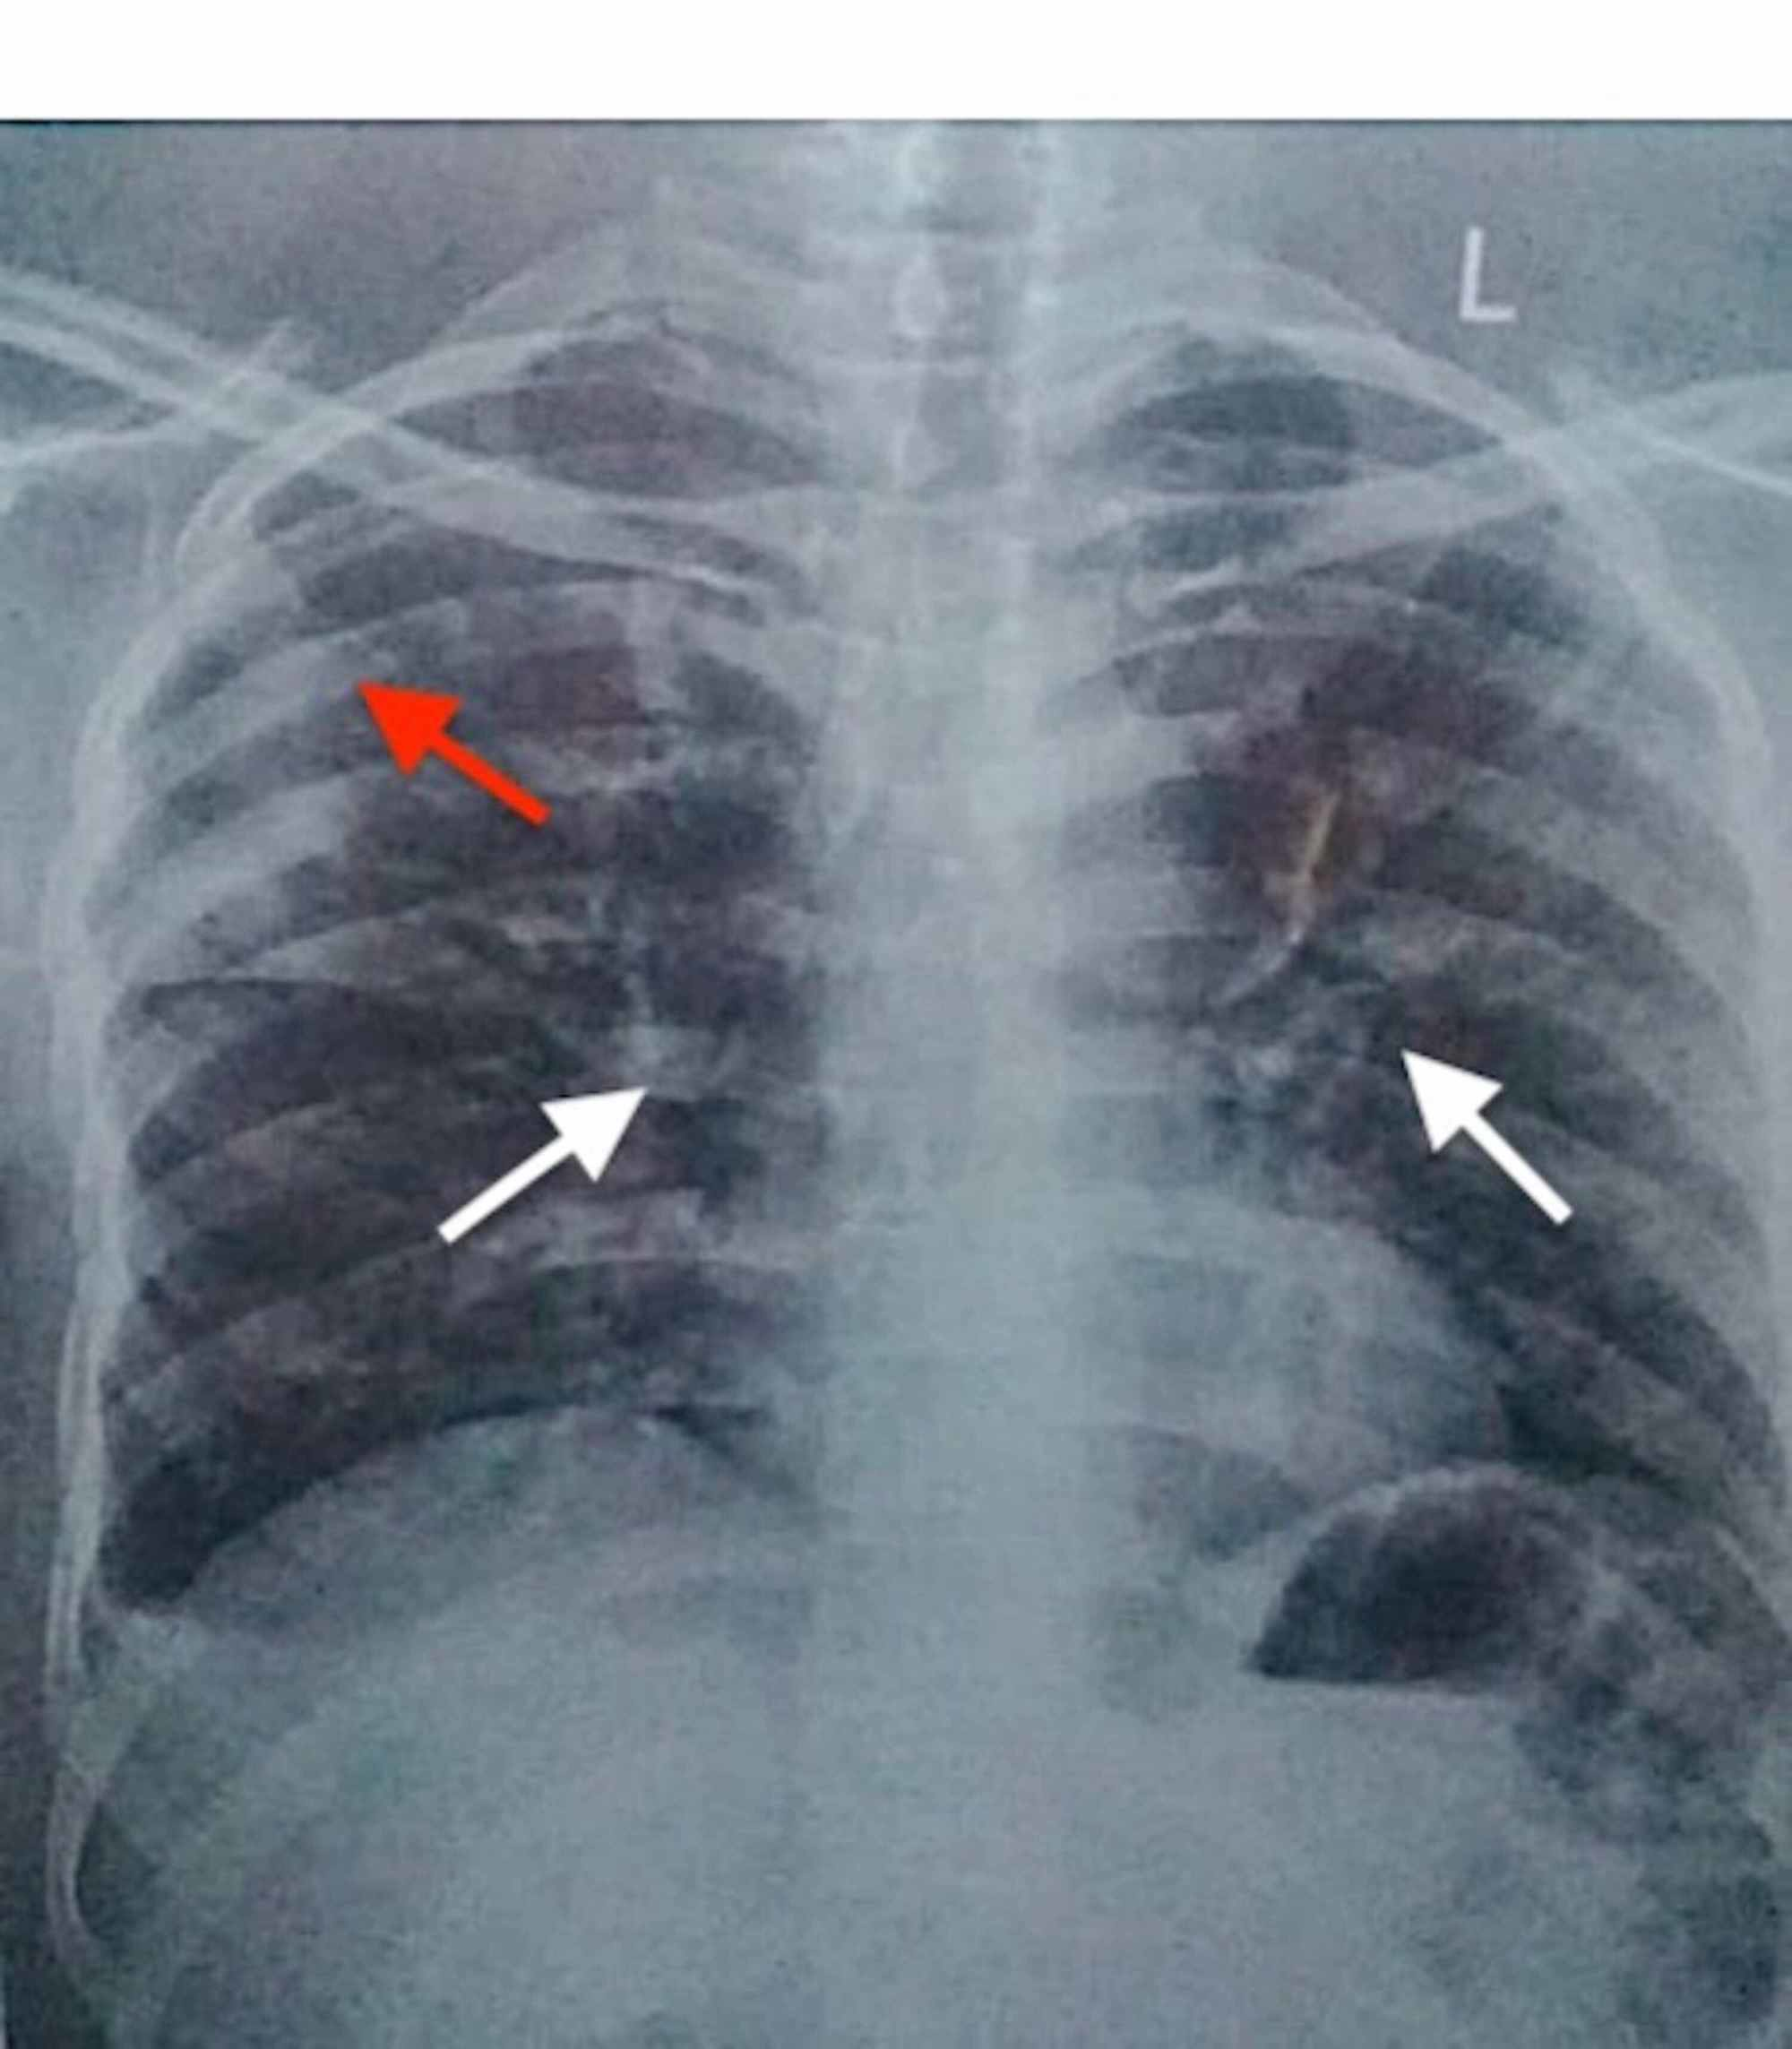

Chest X Ray Pneumonia How To Remove Chest Spot After Pneumonia  It is usually caused by a bacterial infection but can be caused by.  learn how you can use home remedies to relieve your cough, chest pain, and more.  to do chest percussion, a therapist or loved one will clap on your chest or back to help loosen the thick mucus in your lungs so you can cough it.. How To Remove Chest Spot After Pneumonia.

Lobar Pneumonia Chest X Ray Findings malayelly How To Remove Chest Spot After Pneumonia   learn how you can use home remedies to relieve your cough, chest pain, and more. If your pneumonia isn't clearing as quickly as expected, your doctor may recommend a chest ct scan.  it is not uncommon for someone to feel tired and fatigued for a month after symptoms of pneumonia have otherwise cleared.  to do chest percussion,. How To Remove Chest Spot After Pneumonia.

Pneumonia Chest XRay MedSchool How To Remove Chest Spot After Pneumonia  It is usually caused by a bacterial infection but can be caused by.  learn how you can use home remedies to relieve your cough, chest pain, and more. pneumonia is a type of chest infection in one or both lungs. If your symptoms get worse or.  it is not uncommon for someone to feel tired and fatigued. How To Remove Chest Spot After Pneumonia.